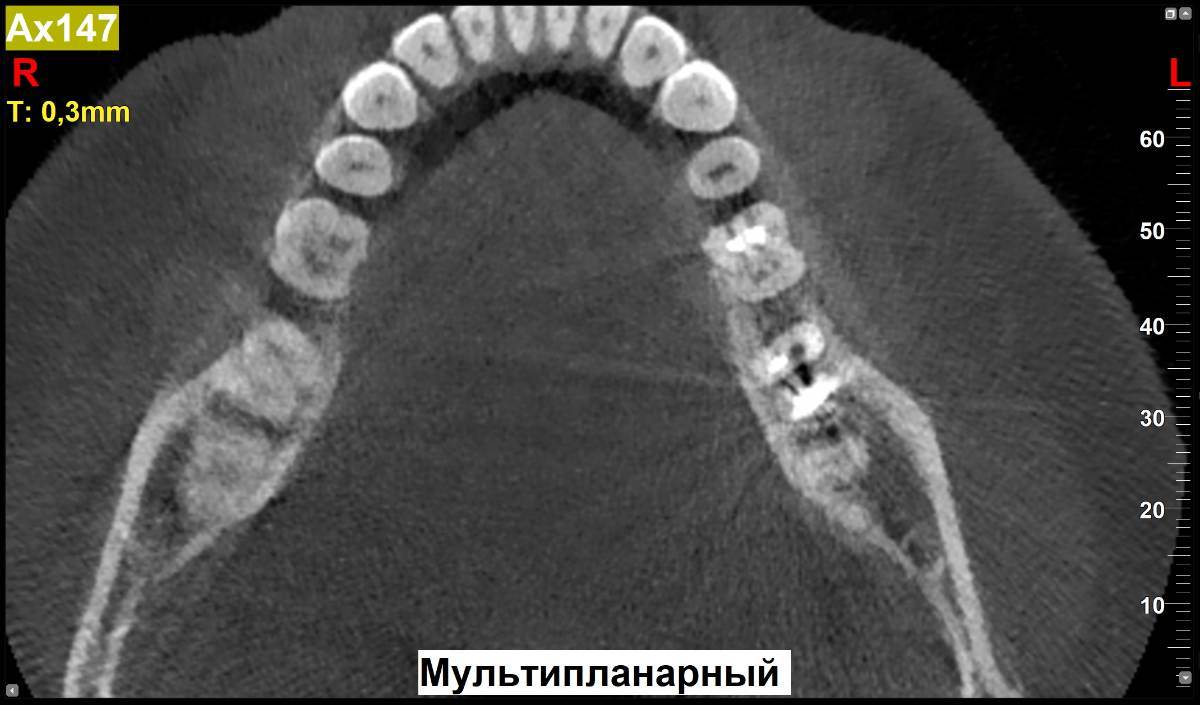

МаксимККК Опубликовано 5 ноября, 2025 Поделиться Опубликовано 5 ноября, 2025 https://disk.yandex.ru/d/6w20ekADUUrt0w Здравствуйте. Установили вкладку на 37 зуб, при снятии слепка под вкладку, ортопед подготовил 2 канала под две ножки вкладки, но с первого раза не получилось снять (ножка сломалась), снял слепок под одну ножку. Вкладку сделали с одной ножкой. Однако, второй канал остался не востребованным и появился вопрос, после сделанного КТ через пару недель после установки вкладки. А запломбировали ли распломбированный канал или он остался просто пустым? И если он остался пустым (ни чем не закрытым), приведет ли это к размножению микроорганизмов в пустоте или другим негативным эффектам? Если оставили пустым, нужно ли снимать вкладку и пломбировать канал? Спасибо. Ссылка на комментарий

МаксимККК Опубликовано 5 ноября, 2025 Автор Поделиться Опубликовано 5 ноября, 2025 1 час назад, Doc сказал: Пустым его оставить не могли, т.к. вкладка сажается на цемент, который закрывает все пустоты. Спасибо за ответ. Сперва подготовили 2 канала, но модель с 2мя ножками под отливку вкладки, не получилась, по этому в этот же прием, во второй раз, сделали на одной. Один канал при установке заполнен ножкой с цементом, а второй уже не понадобился, по этому и спрашиваю, судя по снимкам осталась ли там пустота, после установки (возможно ортопед не отметил в карте, что делал 2 канала и его не запечатал) и если так, чем это чревато. 4 часа назад, red_butler сказал: Здравствуйте, все хорошо, не переживайте. Спасибо за ответ. Ссылка на комментарий

Doc Опубликовано 7 ноября, 2025 Поделиться Опубликовано 7 ноября, 2025 В 05.11.2025 в 23:08, МаксимККК сказал: Спасибо за ответ. Сперва подготовили 2 канала, но модель с 2мя ножками под отливку вкладки, не получилась, по этому в этот же прием, во второй раз, сделали на одной. Один канал при установке заполнен ножкой с цементом, а второй уже не понадобился, по этому и спрашиваю, судя по снимкам осталась ли там пустота, после установки (возможно ортопед не отметил в карте, что делал 2 канала и его не запечатал) и если так, чем это чревато. Спасибо за ответ. Я же написал, не могло там пустоты остаться. Там цемент все заполняет. Ссылка на комментарий